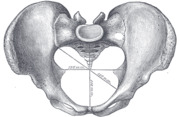

Caldwell–Moloy classification

Throughout the 20th century pelvimetric measurements were made on pregnant women to determine whether a natural birth would be possible, a practice today limited to cases where a specific problem is suspected or following a caesarean delivery. William Edgar Caldwell and Howard Carmen Moloy studied collections of skeletal pelves and thousands of stereoscopic radiograms and finally recognized three types of female pelves plus the masculine type. In 1933 and 1934 they published their typology, including the Greek names since then frequently quoted in various handbooks: Gynaecoid (gyne, woman), anthropoid (anthropos, human being), platypelloid (platys, flat), and android (aner, man). [43][44]

- The gynaecoid pelvis is the so-called normal female pelvis. Its inlet is either slightly oval, with a greater transverse diameter, or round. The interior walls are straight, the subpubic arch wide, the sacrum shows an average to backward inclination, and the greater sciatic notch is well rounded. Because this type is spacious and well proportioned there is little or no difficulty in the birth process. Caldwell and his co-workers found gynaecoid pelves in about 50 per cent of specimens.

- The platypelloid pelvis has a transversally wide, flattened shape, is wide anteriorly, greater sciatic notches of male type, and has a short sacrum that curves inwards reducing the diameters of the lower pelvis. This is similar to the rachitic pelvis where the softened bones widen laterally because of the weight from the upper body resulting in a reduced anteroposterior diameter. Giving birth with this type of pelvis is associated with problems, such as transverse arrest. Less than 3 per cent of women have this pelvis type.

- The android pelvis is a female pelvis with masculine features, including a wedge or heart shaped inlet caused by a prominent sacrum and a triangular anterior segment. The reduced pelvis outlet often causes problems during child birth. In 1939 Caldwell found this type in one third of white women and in one sixth of non-white women.

- The anthropoid pelvis is characterized by an oval shape with a greater anteroposterior diameter. It has straight walls, a small subpubic arch, and large sacrosciatic notches. The sciatic spines are placed widely apart and the sacrum is usually straight resulting in deep non-obstructed pelvis. Caldwell found this type in one quarter of white women and almost half of non-white women.[45]

However, Caldwell and Moloy then complicated this simple fourfold scheme by dividing the pelvic inlet into posterior and anterior segments. They named a pelvis according to the anterior segment and affixed another type according to the character of the posterior segment (i.e. anthropoid-android) and ended up with no less than 14 morphologies. Notwithstanding the popularity of this simple classification, the pelvis is much more complicated than this as the pelvis can have different dimensions at various levels of the birth canal.[46]